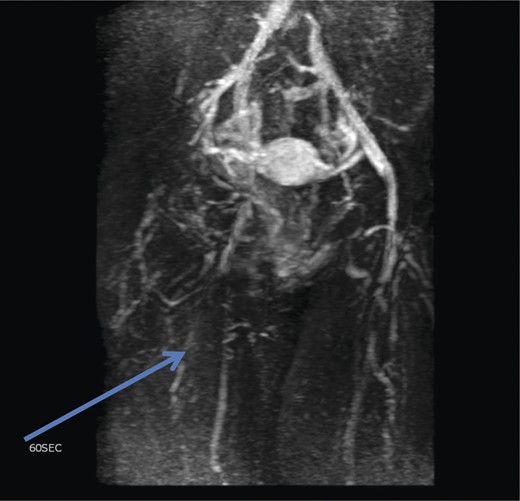

The superficial external pudendal vein was embolized with 1% sodium tetradecyl sulphate and then coiled through a contralateral puncture under fluoroscopic guidance (Figs 3 and 4). The procedure went uneventfully with successful obliteration of the communicating thigh veins to vulval varices (Fig. 5) and the patient was discharged home the same day.

Pre-embolization fluoroscopy showing communication of thigh veins to vulval varices (blue arrow).